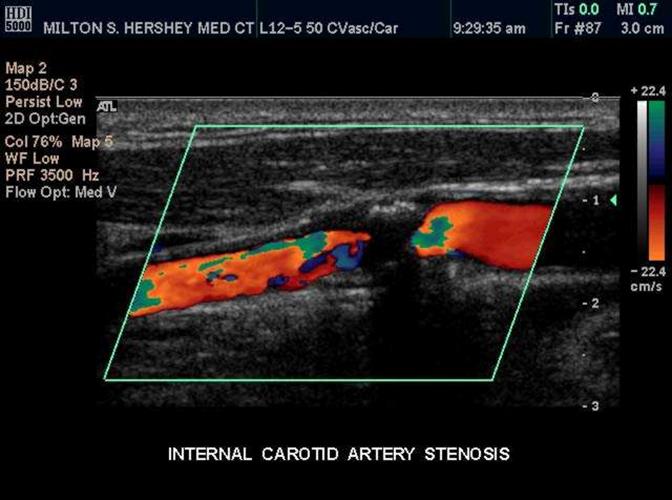

What is Plaque?

Atherosclerotic material that builds up on the walls of arteries

- It restricts flow

- It can break loose

Plaque

A swollen area of the lining of an artery formed by the deposition of lipids

Calcific Plaque

Bright echogenic plaque which creates shadowing

Heterogeneous plaque

more likely to ulcerate

- Nonuniform in echotexture

Ulcerative Plaque

A scooped out appearance

shelf like projections

Occlusion

Complete blockage

- Best used with the terms probable & total

- Complete filling of the vessel internal area with heterogeneous material

- No blood flow